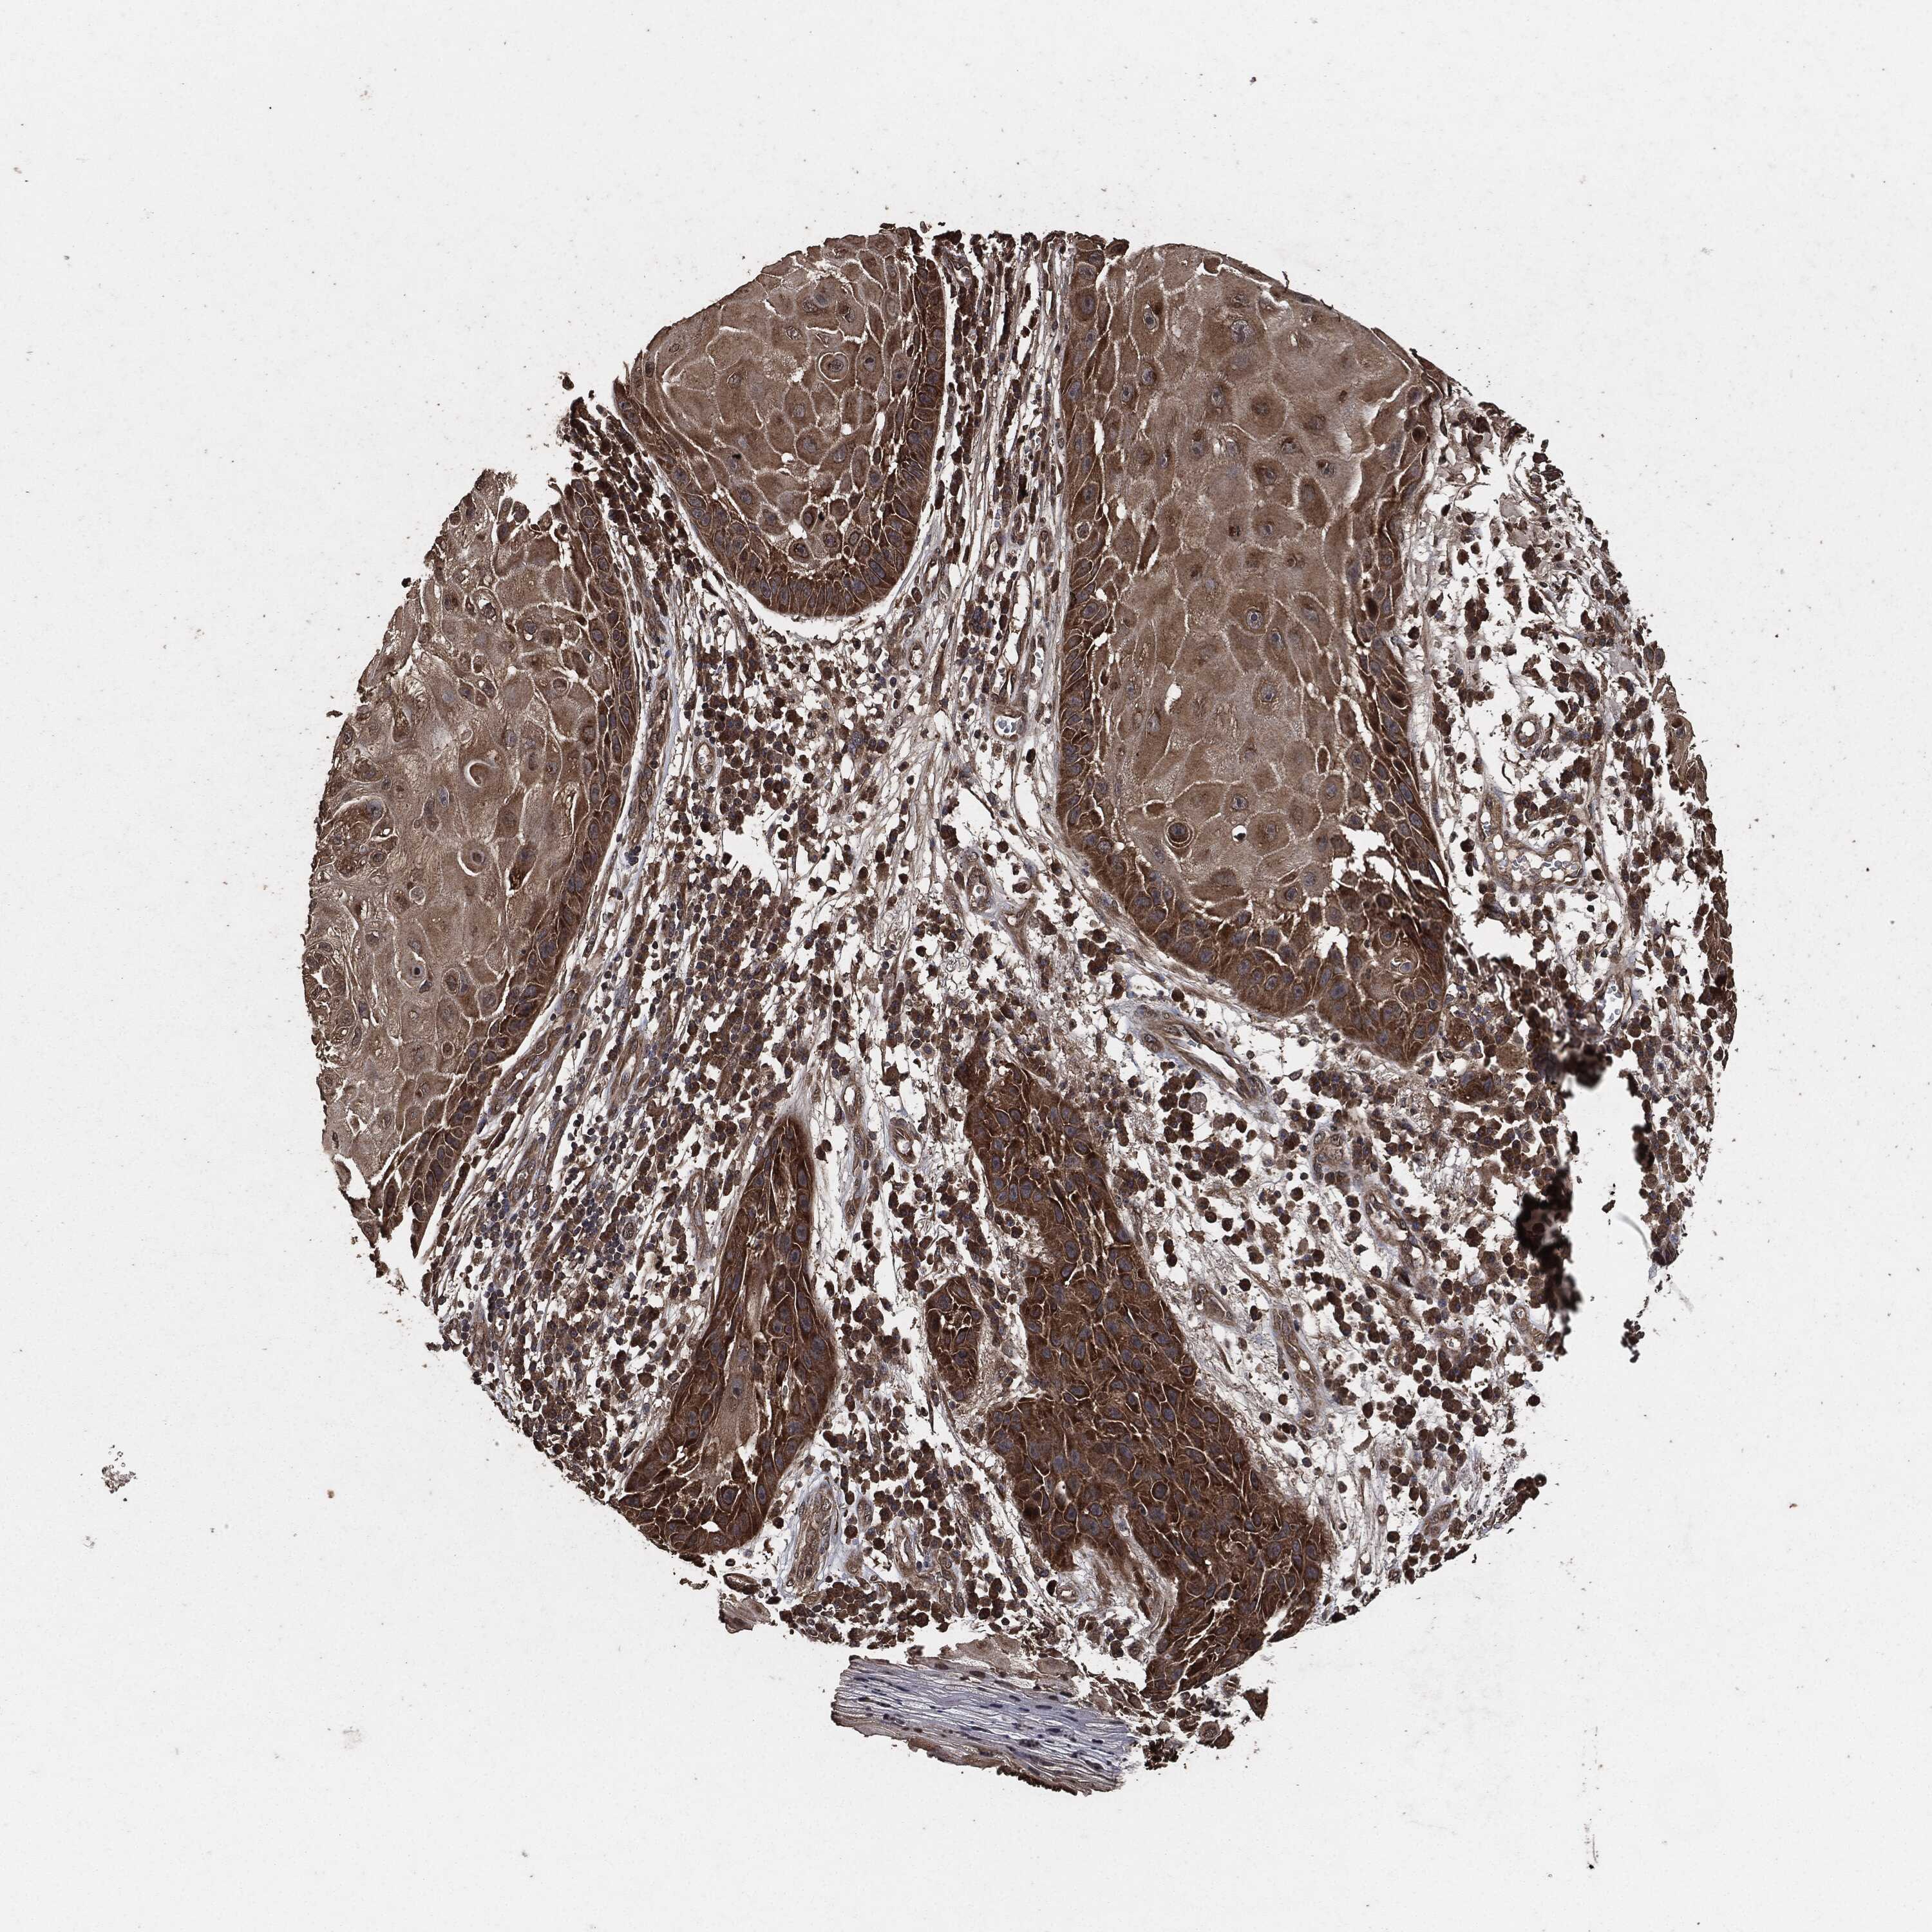

SKIN CANCER - Protein expressioni

A mouse-over function shows sample information and annotation data. Click on an image to view it in a full screen mode. Samples can be filtered based on level of antibody staining by selecting one or several of the following categories: high, medium, low and not detected. The assay and annotation is described here.

Each image is clickable and will lead to virtual microscopy that enables deeper exploration of all samples and also displays staining intensity scores, fraction scores and subcellular localization as well as patient and tissue information for each sample.

Antibody HPA064427

Antibody HPA075510

Staining

High

Medium

Low

Not detected

Intensity

Strong

Moderate

Weak

Negative

Quantity

>75%

75%-25%

<25%

None

Location

Nuclear

Cytoplasmic/membranous

Cytoplasmic/membranous,nuclear

Basal cell carcinoma

BCC, high aggressive

Squamous cell carcinoma, NOS